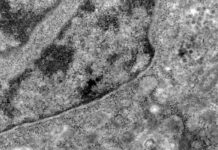

Coronavírus: como a covid-19 danifica o cérebro

Para Julie Helms, tudo começou com um punhado de pacientes da unidade de terapia intensiva (UTI) no Hospital Universitário de Estrasburgo, no...